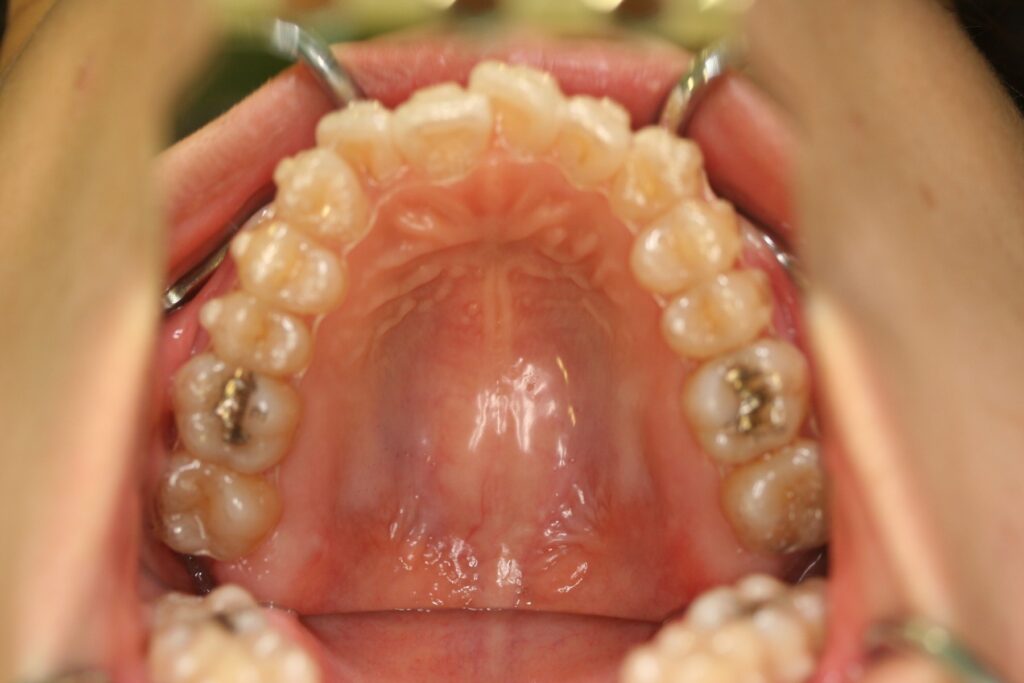

治療実績(症例) アライナー矯正 症例1 上顎前突症例 症例2 上下顎前突症例 症例3 叢生 症例4 開咬 症例5 開咬(外科的矯正治療) アライナー矯正 Post Share Hatena Line RSS feedly Pin it note 1.主訴2.診断名3.初診時年齢4.治療に用いた主な装置とオプション5.抜歯部位6.治療期間・通院回数7.総額と費用内訳総額相談検査・診断料調整料4,000円8.リスク・副作用 治療前 治療中 治療後